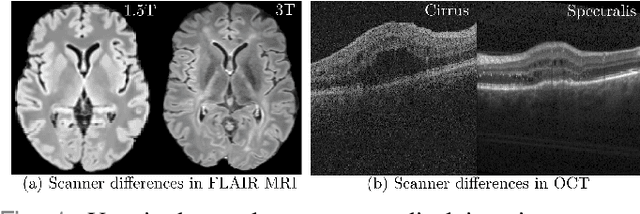

Deep networks are now ubiquitous in large-scale multi-center imaging studies. However, the direct aggregation of images across sites is contraindicated for downstream statistical and deep learning-based image analysis due to inconsistent contrast, resolution, and noise. To this end, in the absence of paired data, variations of Cycle-consistent Generative Adversarial Networks have been used to harmonize image sets between a source and target domain. Importantly, these methods are prone to instability, contrast inversion, intractable manipulation of pathology, and steganographic mappings which limit their reliable adoption in real-world medical imaging. In this work, based on an underlying assumption that morphological shape is consistent across imaging sites, we propose a segmentation-renormalized image translation framework to reduce inter-scanner heterogeneity while preserving anatomical layout. We replace the affine transformations used in the normalization layers within generative networks with trainable scale and shift parameters conditioned on jointly learned anatomical segmentation embeddings to modulate features at every level of translation. We evaluate our methodologies against recent baselines across several imaging modalities (T1w MRI, FLAIR MRI, and OCT) on datasets with and without lesions. Segmentation-renormalization for translation GANs yields superior image harmonization as quantified by Inception distances, demonstrates improved downstream utility via post-hoc segmentation accuracy, and improved robustness to translation perturbation and self-adversarial attacks.